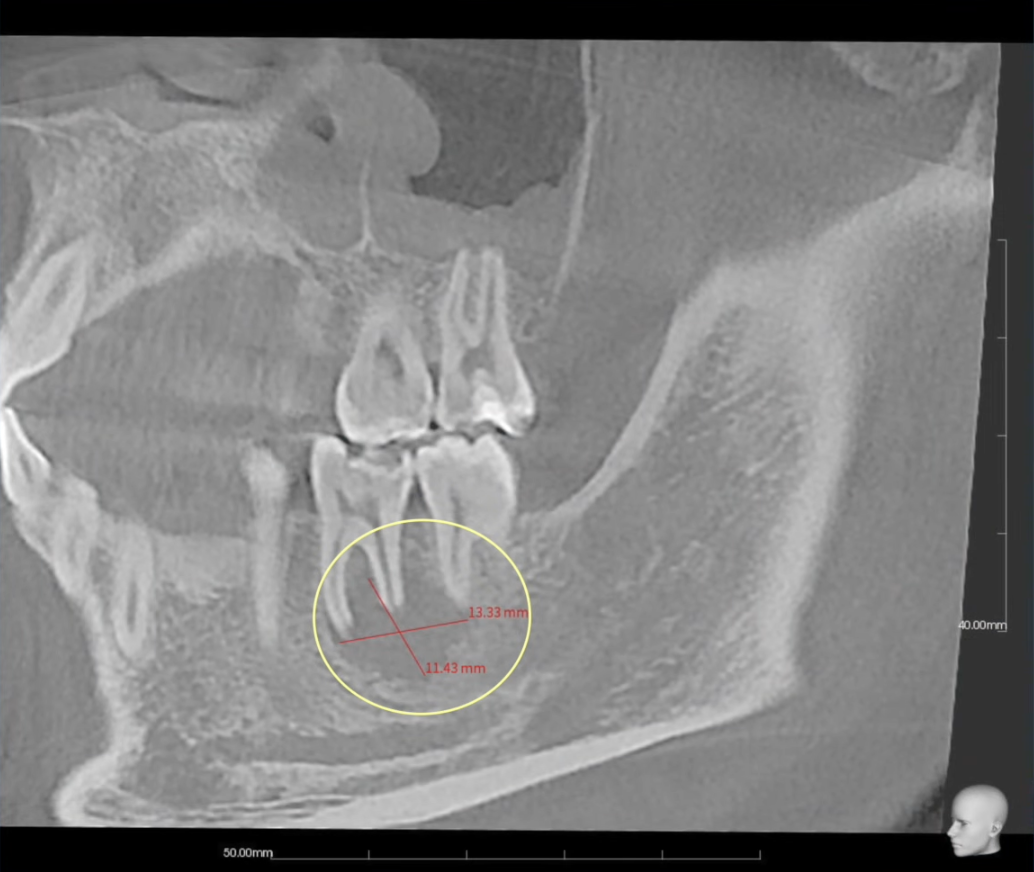

К нам обратился пациент с большим воспалительным очагом. Он затрагивал оба корня зуба и достигал более одного сантиметра в диаметре. Было больно при накусывании, а сам зуб стал подвижным.

В классической школе такой зуб, скорее всего, удалили бы. Но мы решили рассмотреть ситуацию с другой стороны.

Зуб ранее не лечен, корни прямые, каналы доступны для обработки. Поэтому было решено провести эндодонтическое лечение.

Через 9 месяцев на контрольной компьютерной томографии было видно полное восстановление костной ткани.